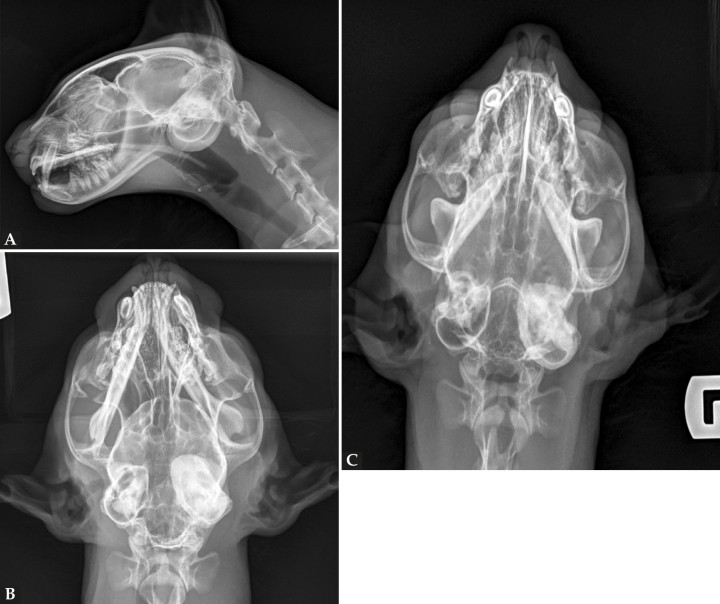

Se realizó un estudio radiográfico de la cabeza del paciente, incluyendo una proyección lateral (Fig. 1A), dorsoventral (Fig. 1B) y rostro 10º ventro-dorsocaudal oblicua (R10ºVCdD) con boca cerrada (Fig. 1C).

Radiografías de la cabeza de un gato maine coon de un año de edad. (A) Proyección lateral. (B) Proyección dorsoventral. (C) Rostro 10º ventro-dorsocaudal oblicua.

En la proyección lateral (Fig. 2A) se observa con buena definición y sin alteraciones la nasofaringe y paladar blando. Una de las bullas timpánicas (BTs) se aprecia aumentada de opacidad con engrosamiento de su pared ventral, no pudiéndose discernir de qué BT se trata al estar superpuestas. En la proyección dorsoventral (Fig. 2B) se identifica la BT izquierda afectada, encontrándose aumentada su opacidad, con paredes engrosadas y escleróticas. El conducto auditivo externo (CAE) izquierdo se encuentra obliterado y con opacidad tejido blando.

En la proyección rostro 10º ventro-dorsocaudal oblicua con boca cerrada (Fig. 2C) se visualizan con mayor claridad los hallazgos descritos previamente, especialmente el compartimento ventromedial de las BTs y sus paredes.

Mismas radiografías que en la Figura 1. (A) Proyección lateral en la que se aprecia aumento de la opacidad a nivel de las bullas timpánicas con engrosamiento de la pared ventral de una de las bullas (cabezas de flecha), nasofaringe con opacidad aire (asterisco) y paladar blando con grosor y posición normal (flecha). (B) Proyección dorsoventral en la que se identifica que la bulla timpánica afectada es la izquierda, aumentada de opacidad y con engrosamiento y esclerosis de sus paredes (asterisco). Además, el conducto auditivo externo izquierdo se encuentra obliterado, con opacidad tejido blando, sin presencia de gas en su interior (cabezas de flecha). (C) Proyección rostro 10º ventro-dorsocaudal oblicua con boca cerrada en la que se aprecia con mayor claridad el compartimento ventromedial de las bullas y sus paredes (flechas).

Las herramientas de diagnóstico por imagen son necesarias para establecer la extensión y el origen del pólipo. Mediante las radiografías se puede valorar si la nasofaringe se encuentra involucrada y ocupada, o si existe desplazamiento ventral del paladar blando, aumento de opacidad de las BT y/o engrosamiento y grado de esclerosis de sus paredes.[ Hammond GJ, Sullivan M, Weinrauch S, King AM. A comparison of the rostrocaudal open mouth and rostro 10 degrees ventro-caudodorsal oblique radiographic views for imaging fluid in the feline tympanic bulla. Vet Radiol Ultrasound 2005; 46(3): 205-209. [PubMed] ] No obstante, para una adecuada evaluación de las BTs la proyección de elección en la especie felina es la rostro 10º ventro-dorsocaudal oblicua con boca cerrada, al aportar un plano de visualización completo de las BTs.[ Hammond GJ, Sullivan M, Weinrauch S, King AM. A comparison of the rostrocaudal open mouth and rostro 10 degrees ventro-caudodorsal oblique radiographic views for imaging fluid in the feline tympanic bulla. Vet Radiol Ultrasound 2005; 46(3): 205-209. [PubMed] ]